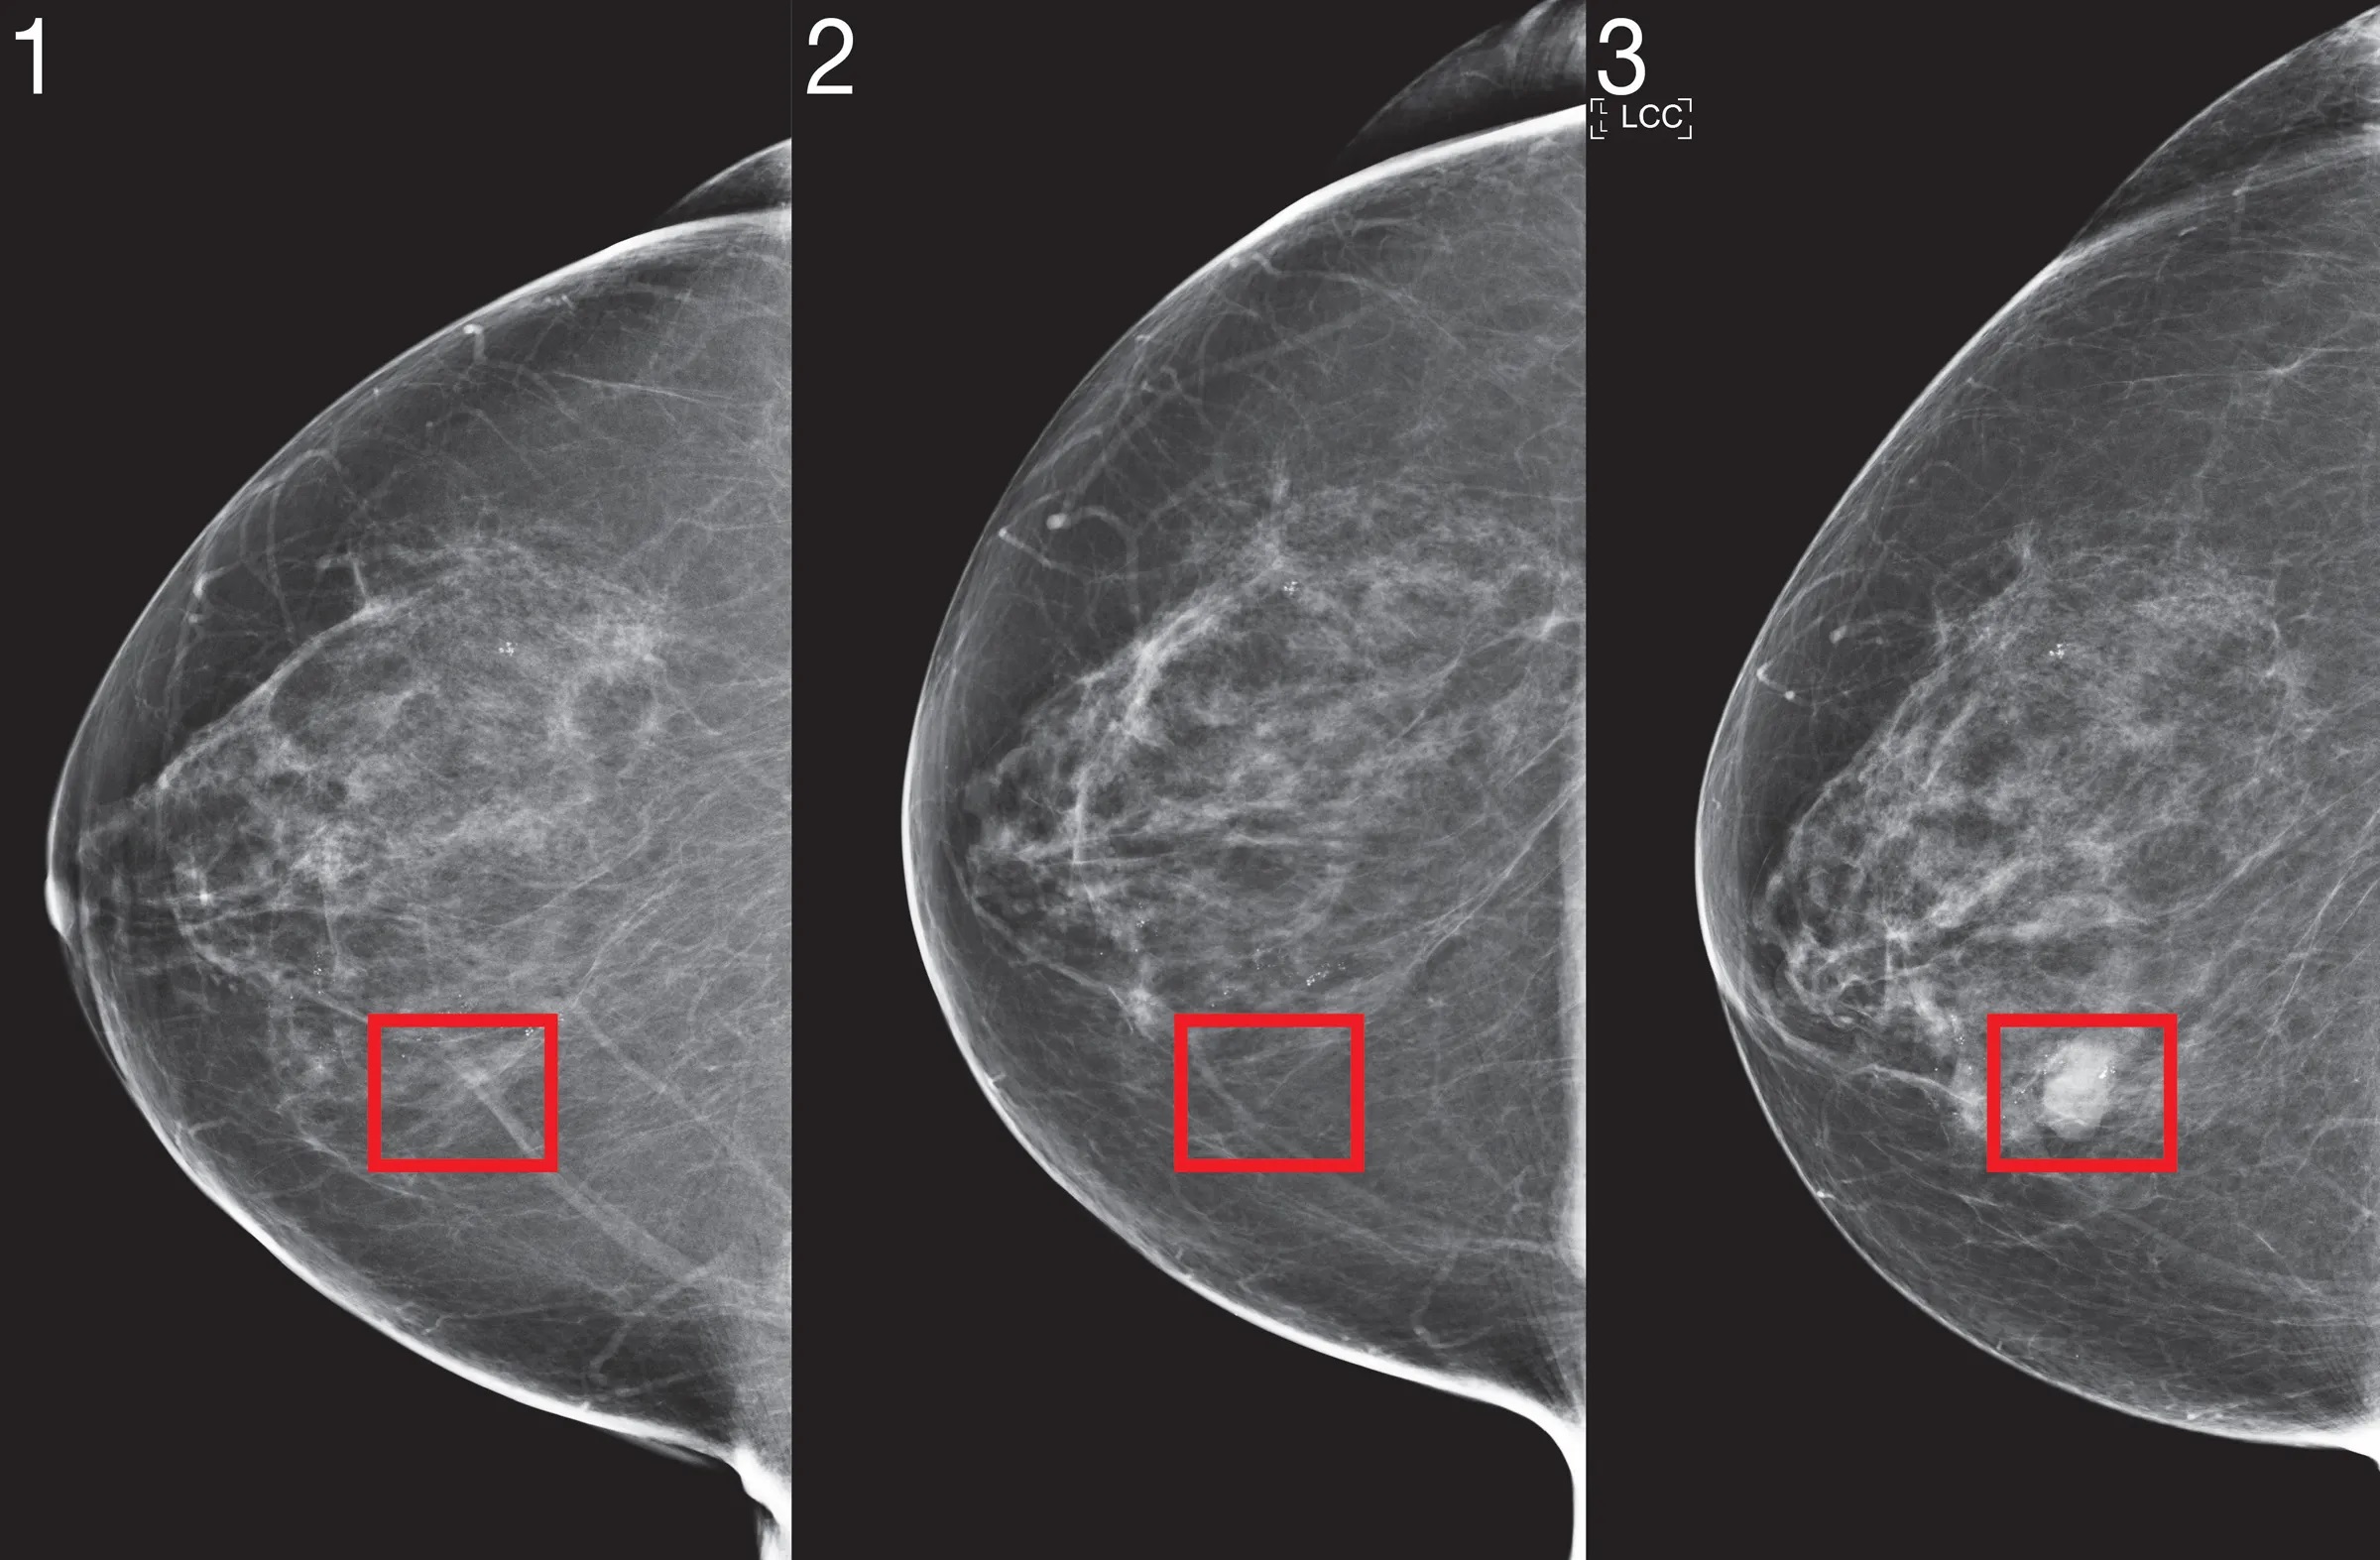

В рамках консультаций по использованию искусственного интеллекта в скрининге рака молочной железы, которые завершилась в прошлом месяце, NSC заявил, что существует "недостаточное количество и качество доказательств, чтобы рекомендовать внедрение этих систем в клиническую практику программы скрининга молочной железы в рамках Национальной службы здравоохранения Великобритании". В заявлении отмечается, что в целом исследования по проверке алгоритмов, используемых для выявления заболевания, были "скудными" и "неприменимыми" к Великобритании, поскольку ни один из наборов данных, использованных в исследованиях, не был получен в Великобритании.

Анализ 12 исследований, посвященных использованию искусственного интеллекта для диагностики рака молочной железы, показал, что "неясно", где эта технология может быть полезной на клиническом пути.

Около 94% из 36 систем искусственного интеллекта, рассмотренных в исследованиях, оказались "менее точными, чем один рентгенолог", и все они оказались менее точными, чем два рентгенолога, обнаружили эксперты из Медицинской школы Уорика. В трех исследованиях алгоритм, используемый для сортировки, регистрировал 10%, 4% и 0% раковых заболеваний из выявленных рентгенологами, что означает, что в некоторых случаях он пропускал 100% случаев, выявленных специалистами.

Анализ, опубликованный в журнале BMJ, также показал, что во многих исследованиях отсутствовала проверка точности работы алгоритма и был отмечен низкий уровень методического качества.

Системы искусственного интеллекта недостаточно специфичны, чтобы заменить двойное чтение радиолога в программах скрининга. Многообещающие результаты небольших исследований не были воспроизведены в более крупных исследованиях.